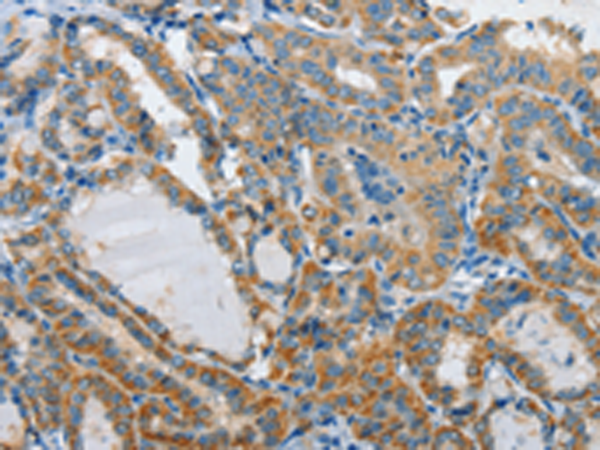

分类: 科研抗体货号: P07324别名:应用: IHC反应种属: Human, Mouse, Rat